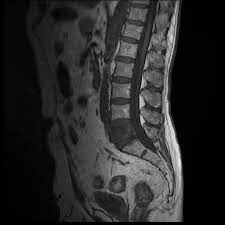

Metastatic Disease Of Spine Pathology Orthobullets

Metastatic Disease Of Spine Pathology Orthobullets from upload.orthobullets.com